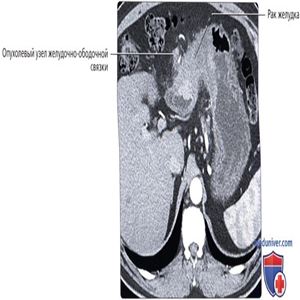

КТ с контрастированием, аксиальный срез: выраженное утолщение стенки дистального отдела желудка. Обратите внимание на обособленный опухолевый узел, расположенный в жировой ткани между желудком и поперечно-ободочной кишкой и являющийся признаком распространения опухоли в желудочно-ободочную связку. Желудочно-ободочная связка служит потенциальным проводником при распространении злокачественного новообразования желудка в прилежащие отделы толстой кишки.

КТ с контрастированием, более каудальный срез: определяется опухолевый очаг в желудочно-ободочной связке—части большого сальника, соединяющей большую кривизну желудка с поперечно-ободочной кишкой. Опухоль искривляет и сужает просвет поперечно-ободочной кишки.